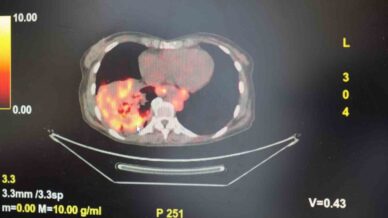

• sigarasiz akciger kanseri vakalarinda dikkat ceken artis BnnyeLcP

’Sigarasız akciğer kanseri’ vakalarında dikkat çeken artış

Göğüs Hastalıkları Uzmanı Prof. Dr. Şevket Özkaya, son yıllarda sigara kullanmayan bireylerde de akciğer kanseri olaylarının dikkat çeken bir oranda arttığını belirterek, bilhassa bayanlarda görülen adenokarsinom tipi akciğer kanserinin artış gösterdiğine dikkat çekti. Bu mevzuda yapılan son araştırmalara değinen Özkaya, akciğer kanseri teşhislerin...